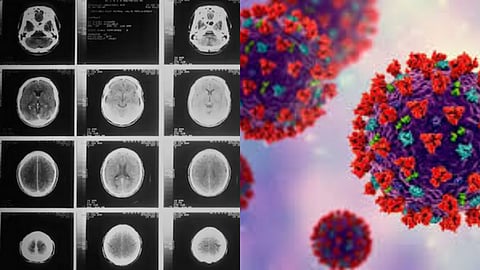

கொரோனா பெருந்தொற்றால் முதிர்ச்சி அடையும் மனிதர்களின் மூளை.. ஆய்வில் அதிர்ச்சி..!

கொரோனா பெருந்தொற்றால், மனிதர்களின் மூளை வழக்கத்தை விட ஆறு மாதங்கள் முதிர்ச்சி அடைந்துள்ளதாக புதிய ஆய்வில் தெரியவந்துள்ளது. இங்கிலாந்திலுள்ள நாட்டிங்ஹாம் பல்கலைக்கழக (Nottingham University) ஆராய்ச்சியாளர்கள் நடத்திய ஆய்வில், கொரோனாவால் பாதிக்கப்பட்டவர்கள் மட்டுமல்லாமல், பாதிக்கப்படாதவர்களின் மூளையின் செயல்பாடுகளும் கூட வேகமாக வயதாகியிருப்பதை கண்டறிந்துள்ளனர்..கொரோனா ஊரடங்கு காலத்தில் மக்கள் சந்தித்த சமூக விலகல், தனிமை, தொடர்ச்சியான மன அழுத்தம் மற்றும் ஒழுங்கற்ற வாழ்க்கை முறையும் மூளையின் செயல்பாடுகளை பெரிய அளவில் பாதித்துள்ளதாக ஆய்வில் தெரிவிக்கப்பட்டுள்ளது.

மேலும் கொரோனா காலத்தில், பாதிக்கப்படாதவர்களில், மூளையின் செயல்பாடுகளும் வேகமாக வயதாகியிருப்பதை கண்டறிந்துள்ளனர்.. இதில் ஆண்களே அதிகமாக பாதிக்கப்பட்டுள்ளனர் என்பதையும் இது கண்டறிந்துள்ளது. நேச்சர் கம்யூனிகேஷன்ஸில் வெளியிட்ட இந்த ஆய்வு, சமூகம், தனிமை, வாழ்க்கை முறை சீர்குலைவுகள் மற்றும் மன அழுத்தம் ஆகியவற்றால் குறிக்கப்பட்ட நேரத்தை மக்கள் எதிர்கொண்ட தொற்றுநோய் காலத்தை பகுப்பாய்வு செய்தது.

கொரோனா நோய்த்தொற்றுகள் வயதானவர்களில் நரம்புச் சிதைவு மற்றும் அறிவாற்றல் வீழ்ச்சியை மோசமாக்கியுள்ளன என்பதை பல ஆய்வுகள் கண்டறிந்துள்ளன. ஆனால் இந்த புதிய ஆராய்ச்சி மக்கள் இன்னும் தொற்றுநோயால் எவ்வாறு பாதிக்கப்படுகிறார்கள் என்பதை ஆராய்கிறது. அதாவது கொரோனா காலத்தில் வந்த கொரோனா தொற்றால் இன்றும் மக்கள் எந்த அளவிற்கு பாதிப்புக்கு உள்ளாகி வருகின்றனர் என்பதை இந்த ஆய்வு சொல்கிறது..